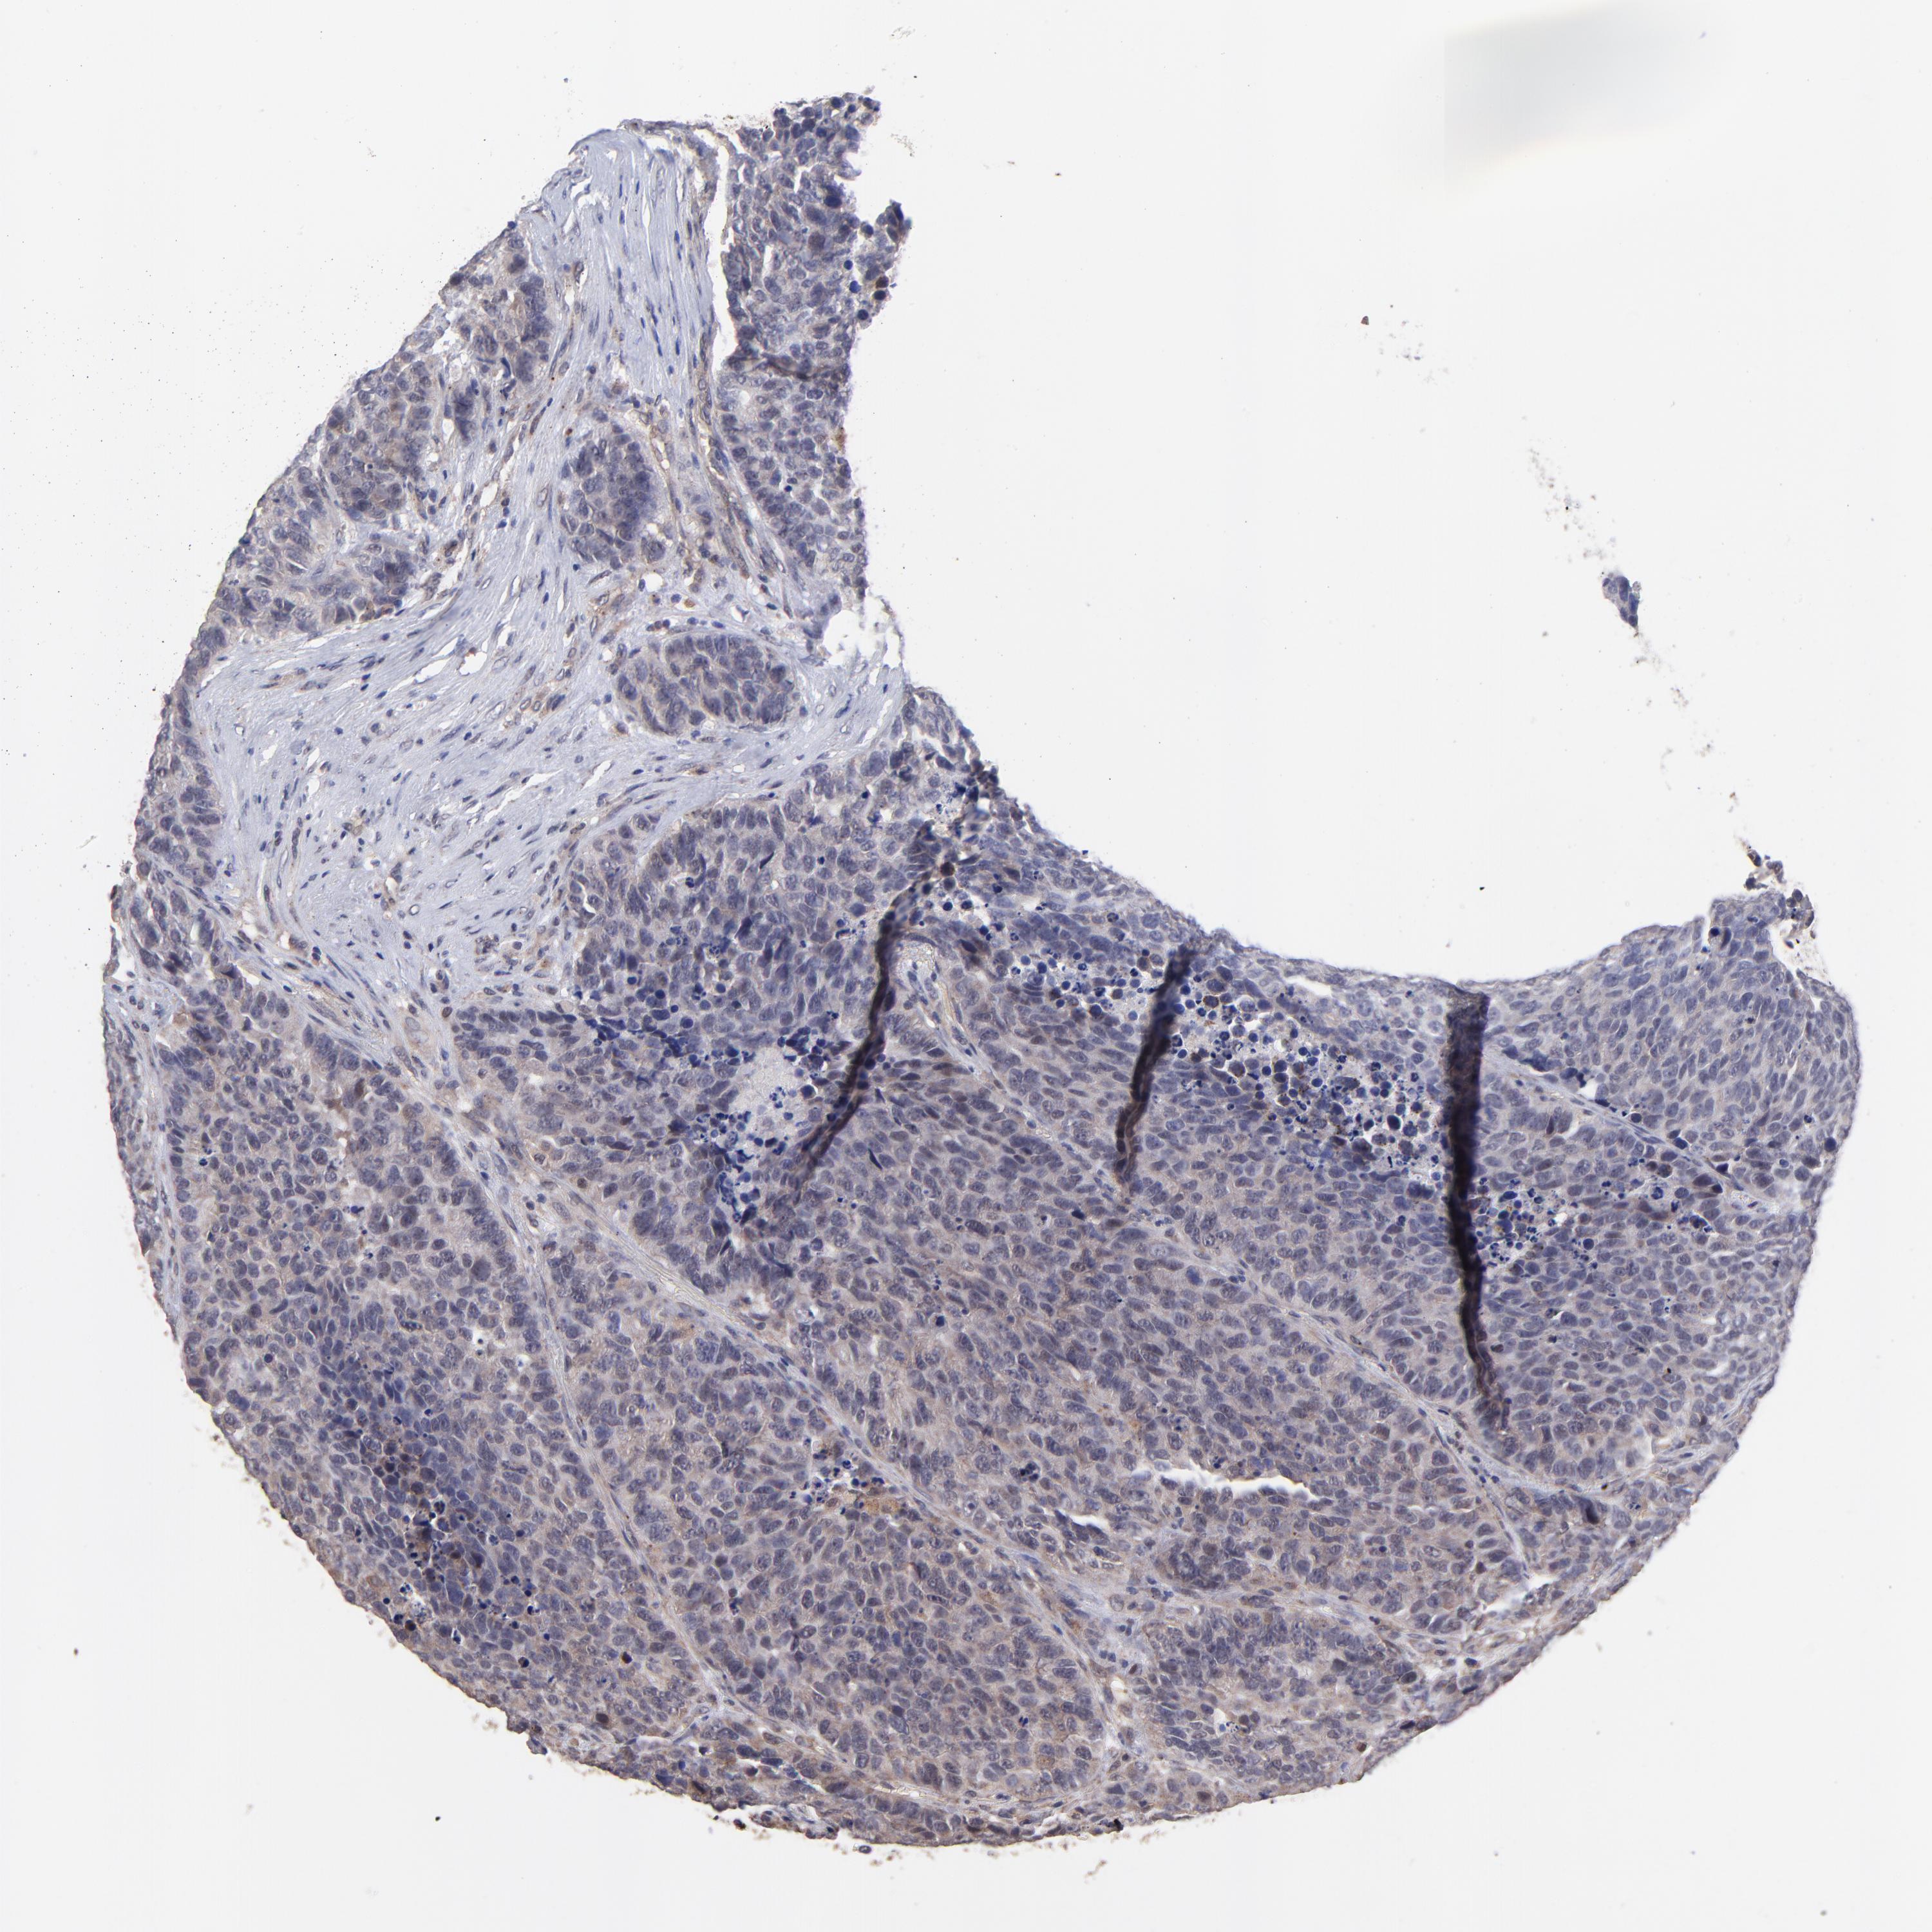

CARCINOID - Protein expressioni

A mouse-over function shows sample information and annotation data. Click on an image to view it in a full screen mode. Samples can be filtered based on level of antibody staining by selecting one or several of the following categories: high, medium, low and not detected. The assay and annotation is described here.

Antibody stainingi

Antibody staining in the annotated cell types in the current human tissue is reported as not detected, low, medium, or high, based on conventional immunohistochemistry profiling in selected tissues. This score is based on the combination of the staining intensity and fraction of stained cells.

Each image is clickable and will lead to virtual microscopy that enables deeper exploration of all samples and also displays staining intensity scores, fraction scores and subcellular localization as well as patient and tissue information for each sample.

Antibody HPA003203

Staining

High

Medium

Low

Not detected

Intensity

Strong

Moderate

Weak

Negative

Quantity

>75%

75%-25%

<25%

None

Location

Nuclear

Cytoplasmic/membranous

Cytoplasmic/membranous,nuclear

Carcinoid, malignant, NOS